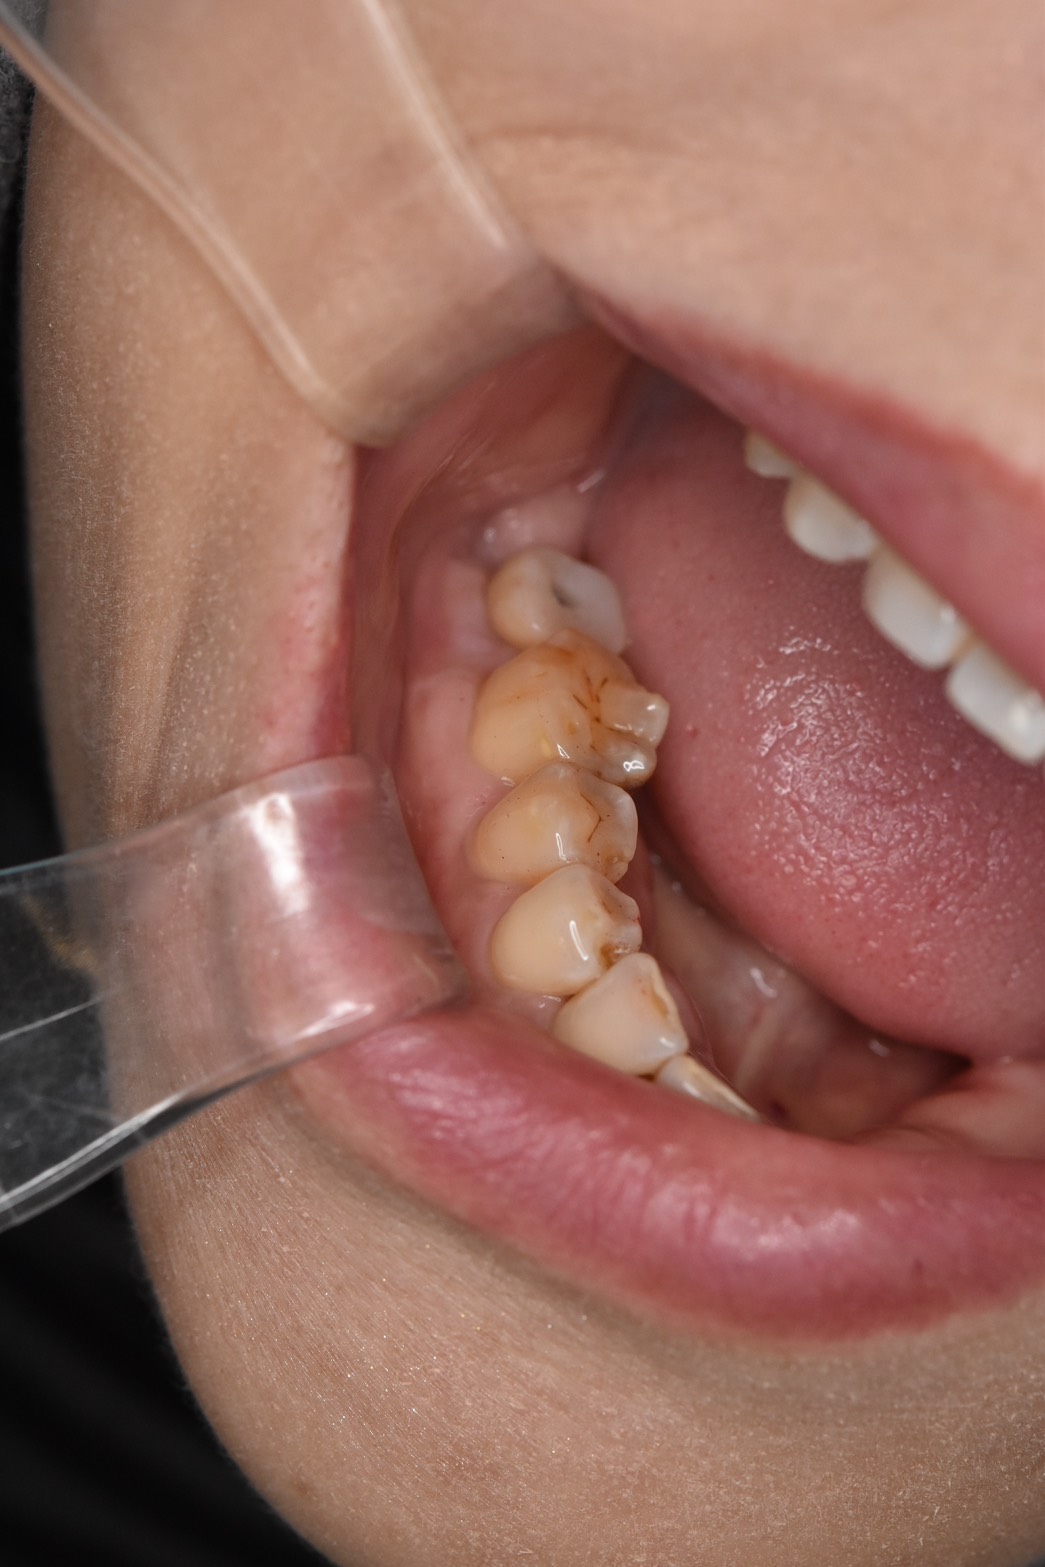

欠損部位に対応する対顎の歯が挺出(伸長)しており、噛み合わせのスペースが限られている状態でした。

この状態では、一般的な補綴設計が難しく、治療方針の検討が必要なケースでした。

インプラント症例(60代以上、術前)下顎左側欠損部の口腔内写真。対顎歯の伸長が見られる

そのため、噛み合わせのバランスを優先し、補綴物の高さを調整する設計としています。

対顎歯の伸長がある症例では、理想的な高さでの補綴が難しい場合があります。

本症例では、削合によるリスクを避けるため、噛み合わせの安定を優先した治療を行いました。

対顎の歯が伸びていたため、削合や矯正が難しいケースでは、噛み合わせの調整を優先し、あえて補綴物の高さを変えることがあります。今回の患者さまは、削合するとしみるリスクがあると考えられたため、その方針をとりました。